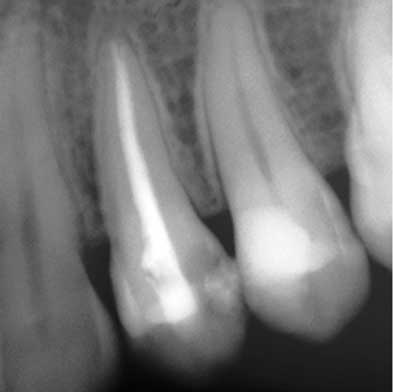

Endodoncia

Dra. Carmen Feito Bárcena